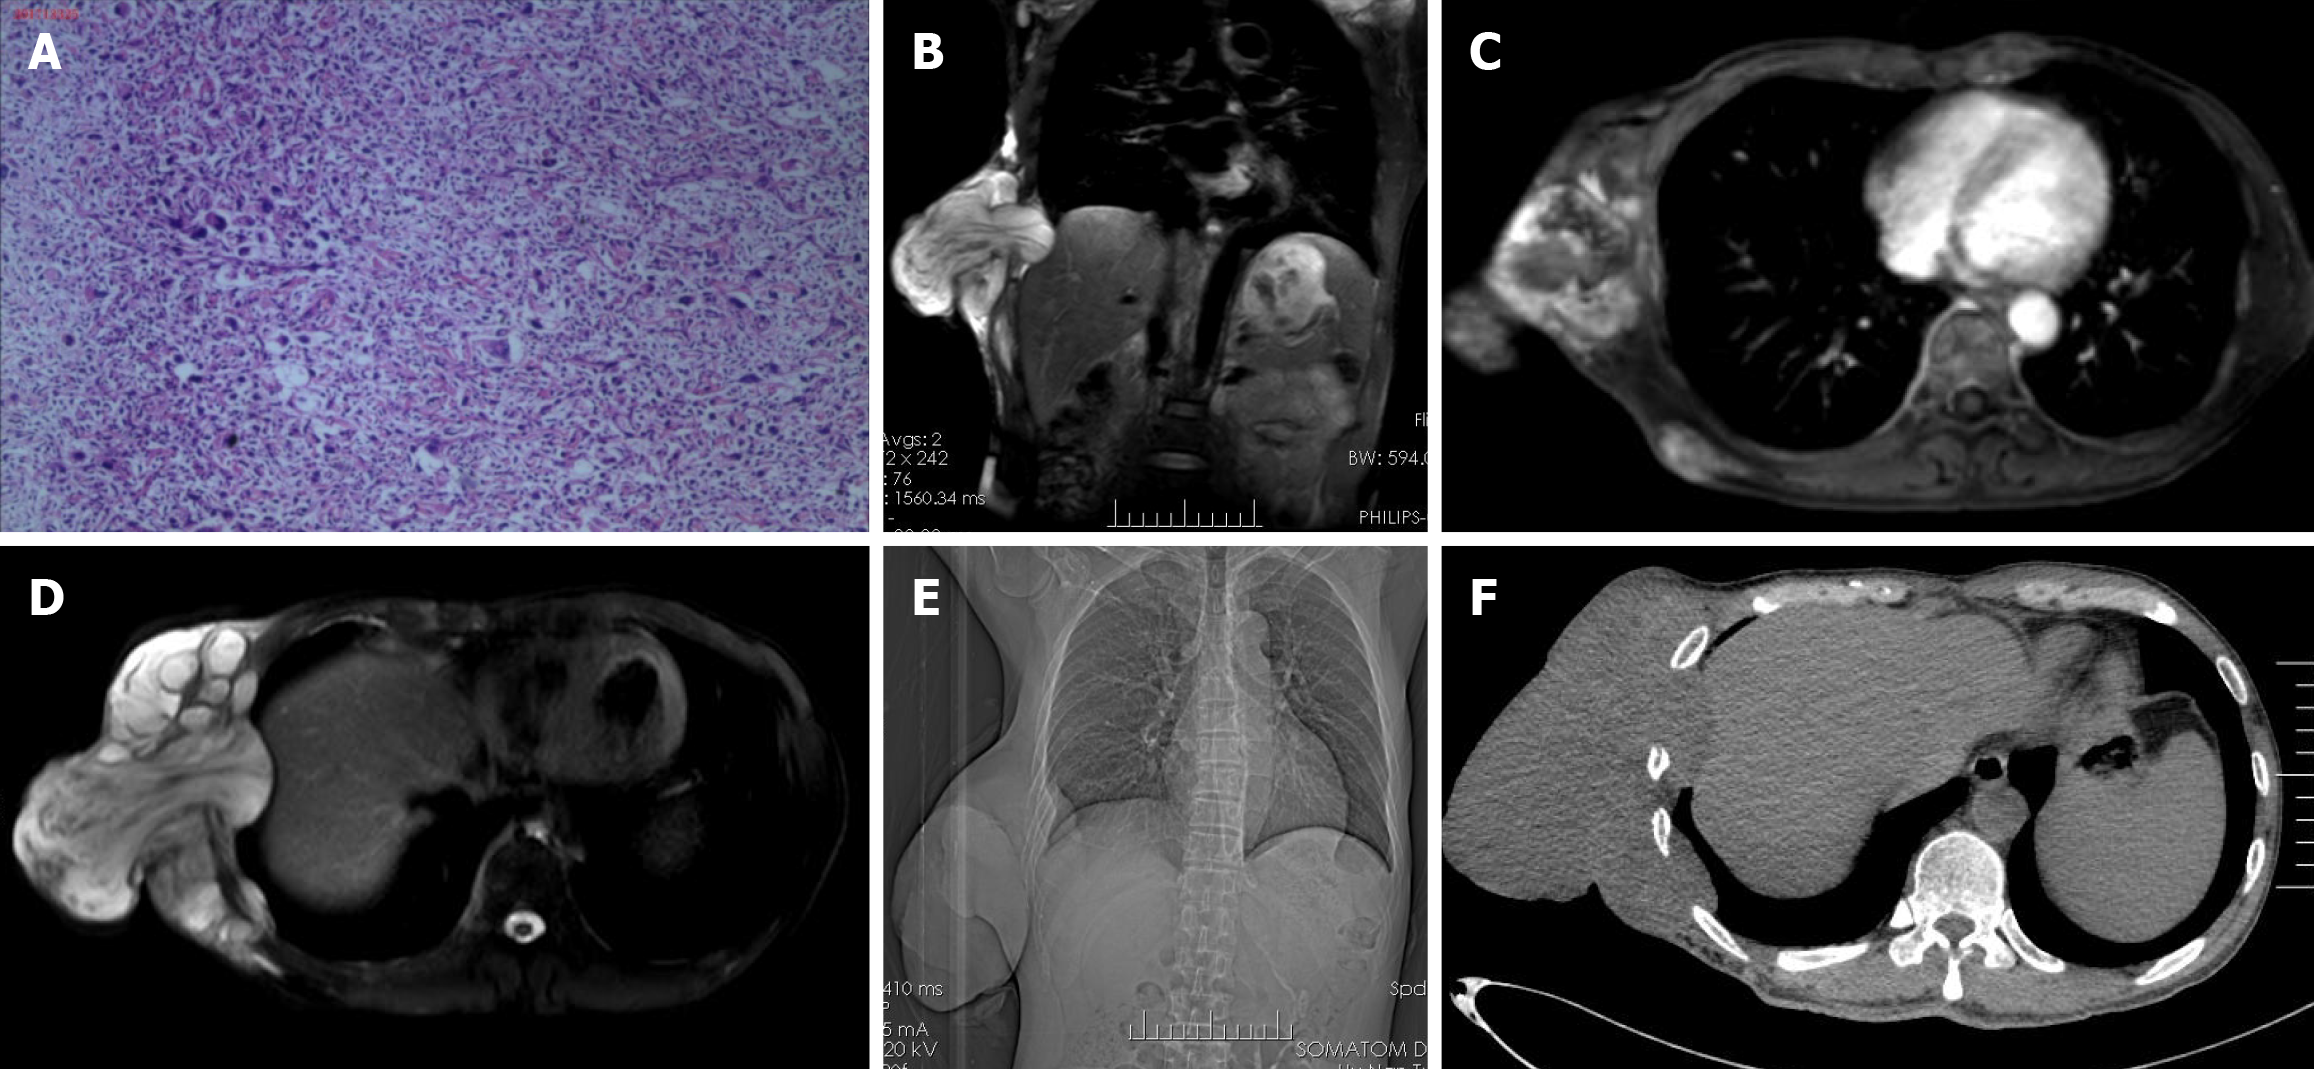

A 56-year-old male patient presented with a bean-sized mass on his right lower chest wall. The mass was primarily observed in 2006 and resected in a local hospital. The resected mass was pathologically confirmed as low-grade MFS at Hunan Cancer Hospital. The patient did not receive subsequent treatment. In 2008, the mass reappeared and was resected again in the same hospital. The second pathology diagnosis was comparable to the initial diagnosis (Figure 1A). After that, the patient experienced multiple surgeries to treat the mass as before. During multiple treatments, the lesion's border gradually extended, and its size increased rapidly. Upon this hospitalization, the large mass protruded out of the chest wall, and ulceration formed with heavy exudation.

The results of magnetic resonance imaging (MRI) and computed tomography (CT) suggested that the lesions had invaded the chest wall and ribs. Multiple nodules, suspected as metastatic lesions, were found in both lungs (Figure 1B-F). Furthermore, two enlarged lymph nodes were detected in the right auxiliary fossa by ultrasonography, and malignant cells were identified by needle biopsy. Although an obvious abnormality was not observed in the abdominal organs by ultrasonography, radioactive accumulation in the right 6th-8th ribs was detected by bone scanning and was suspected to be a metastatic lesion.

Pathological results confirmed the lesion (18 cm × 14 cm × 9 cm) as recurrent MFS (Figure 1A). Microscopic images depicted common characteristics of MFS, including dominant tissue structural distortion in fibrous and histiocyte cells, emergence of heteromultinuclear giant cells, high nucleus/cytoplasm ratio, and sporadic inflammation cells. Though adjacent to the lesion, no infiltration was detected in the ribs. In addition to the inflammatory changes caused by fibrosis calcification in the right lung nodule, no metastatic lesion was detected in the auxiliary fossa lymph node. This indicates that no residual tumor was detected at the skin’s cutting edge or at the bottom, and was therefore a good prognostic sign.